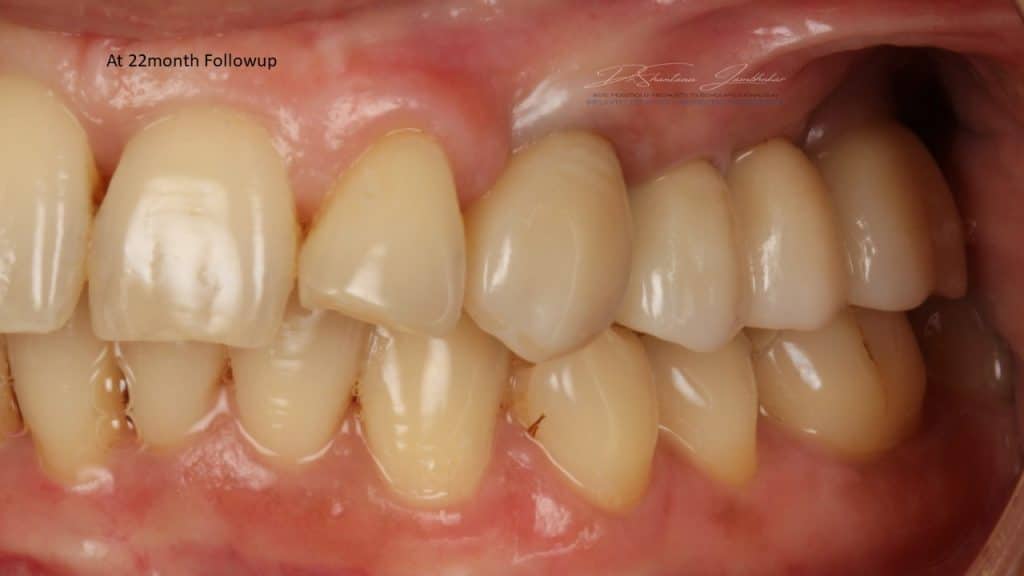

Post Treatment Follow up at 22 months

IOPA at 22 month Follow up